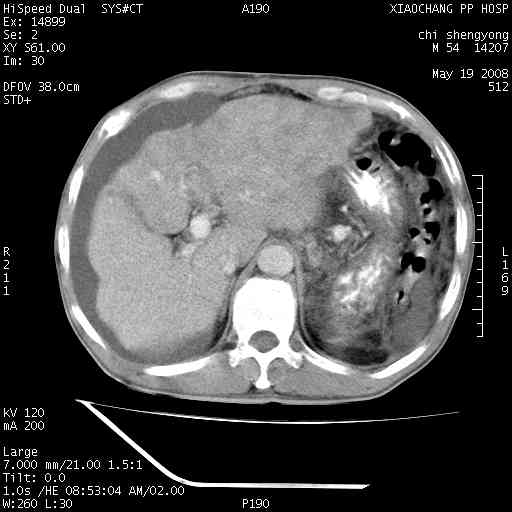

以下是引用zjzjr在2008-5-21 10:52:00的发言:[br]肝左叶巨块型肝癌伴门静脉左支瘤栓形成.肝硬化、腹水,胃底静脉曲张,脾术后改变。

以下是引用随光逐影在2008-5-21 16:20:00的发言:[br]1)肝左叶肝癌伴门静脉左支瘤栓形成,腹膜后淋巴结转移。2)肝硬化、腹水、胃底静脉曲张。3)胆囊炎。4)脾脏缺如,为切除术后所致。